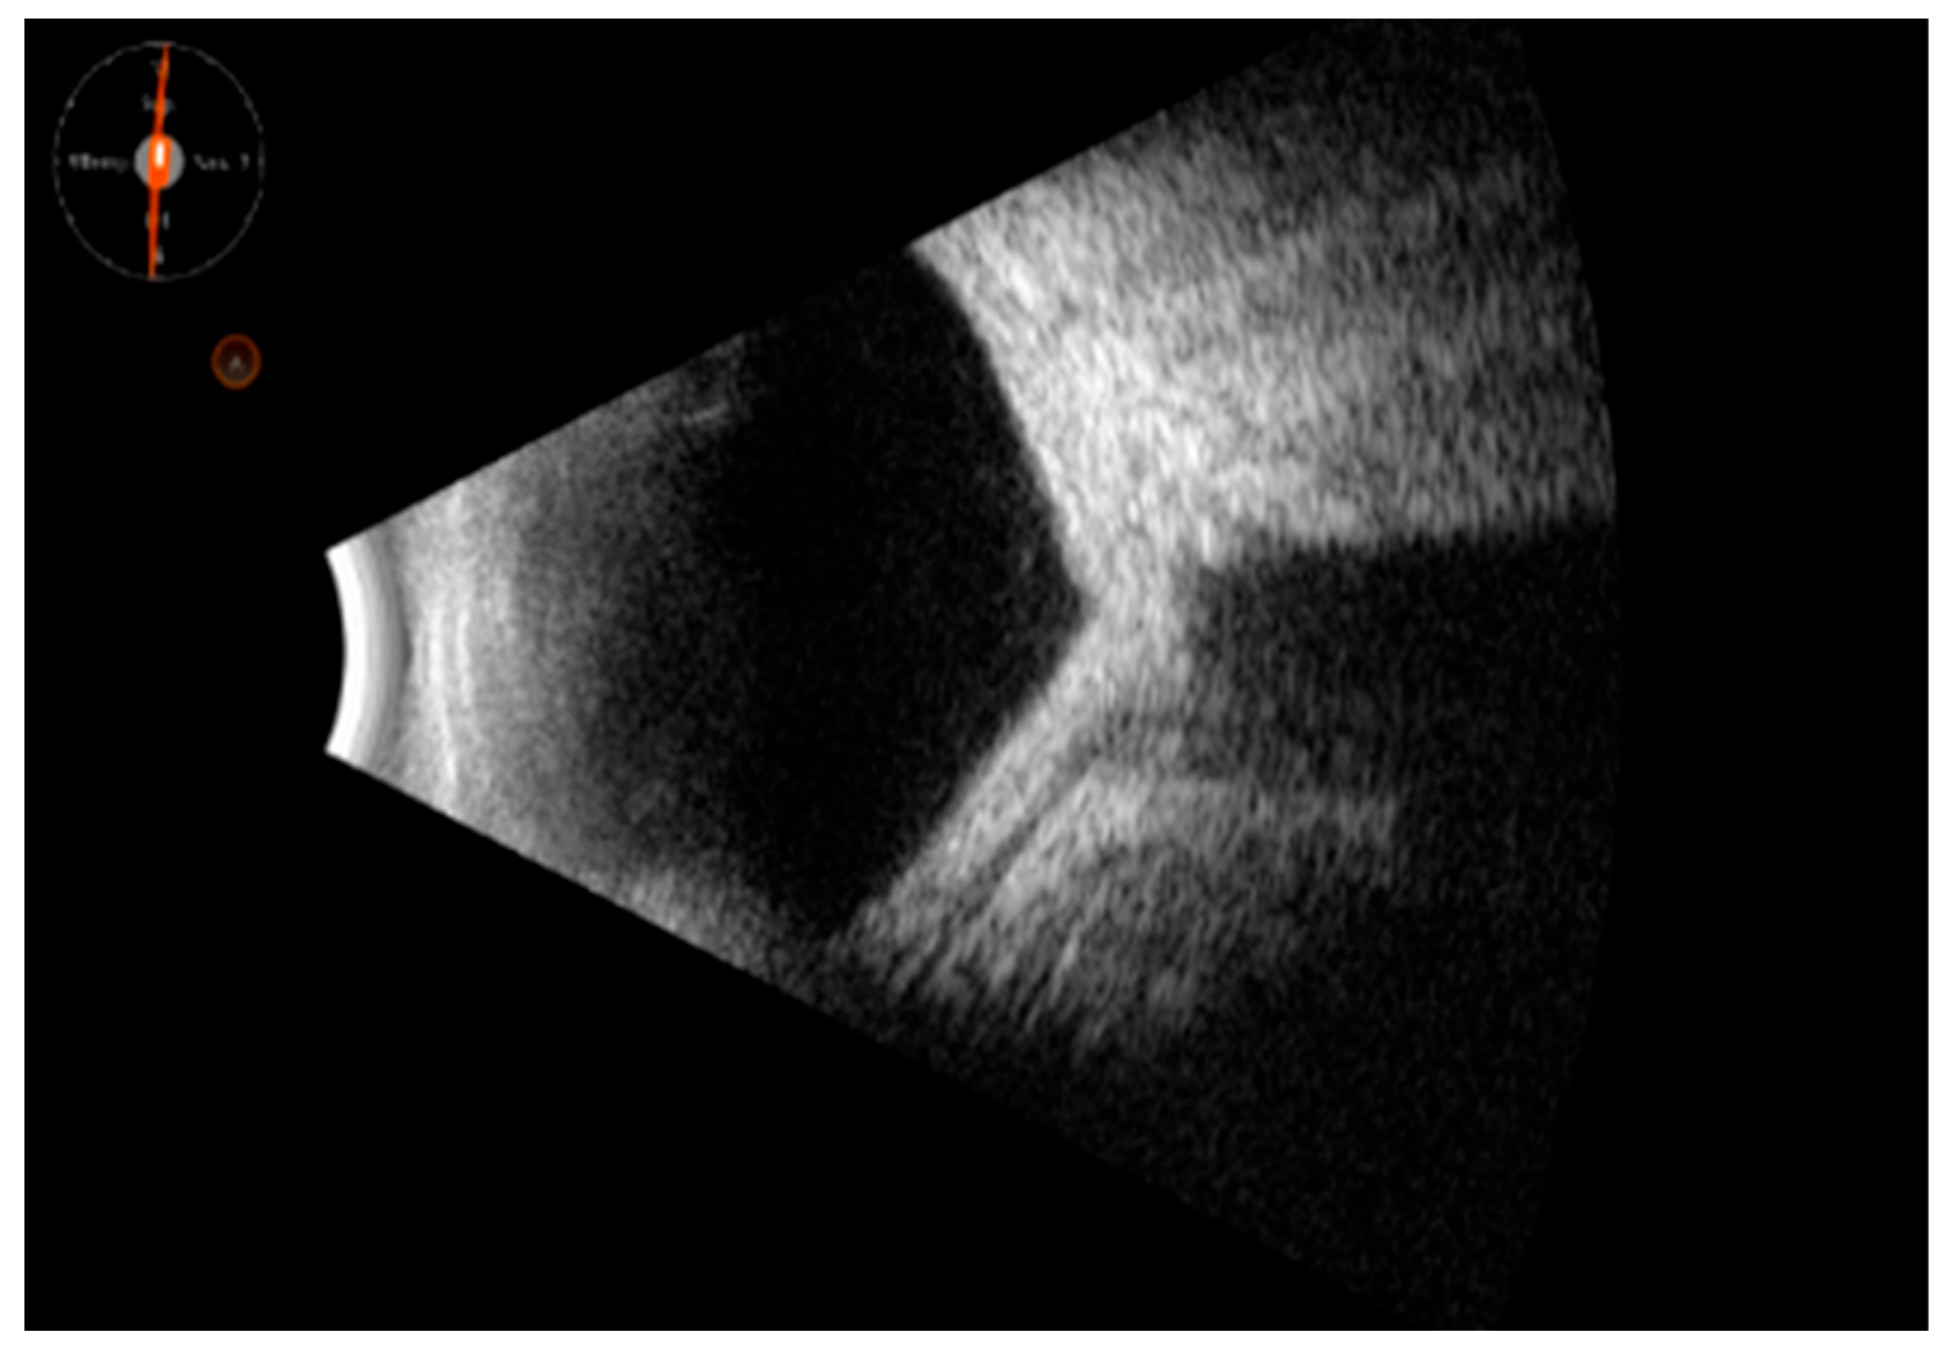

Vitreous patterns: The vitreous appeared with abundant corpuscular movements (vitreous corpuscles), and the posterior vitreous seemed organized into blocks or clouds, with or without vitreous detachment. Vitreous corpuscles could be classified as follows: 1. mild (finely dispersed forward of the posterior vitreous), 2. moderate (coarsely organized on the posterior vitreous, with or without highly reflective membranes), 3. severe (abundant haze located in the entire vitreous cavity forward of the posterior vitreous with or without highly reflective membranes).

In the UMSs, vitreous corpuscles could comprise inflammatory cells, purulent inflammatory cell, tumor cells, or vitreous metastasis. The intensity of the vitreous corpuscles or their mobility alone could not allow us to pinpoint the UMS (inflammatory, infectious, neoplastic, metastatic). Nevertheless, we noted that more frequently infectious forms (sarcoidosis, tuberculosis, candidiasis) could result in a moderate or severe form, even in association with hyperreflective membranes. Unlike the other infectious forms, however, ocular infection with toxoplasma gondii caused an ultrasound picture of severe vitreous corpuscles but not associated with hyperreflective membranes, and the focus of infection was often not revealed by B-scan ultrasound.

Representative images are given in Figure 1, Figure 2 and Figure 3.

Figure 1. Ultrasound findings in mild, moderate, and severe vitritis. (A) Slight vitreous corpuscles collected in “clouds” with minimal increase in chorioretinal thickness (syphilis); (B) moderate vitreous corpuscles with a high mobility, organized in posterior clusters. The main aspect of the vitreous body is its high cellularity, which is accompanied by abnormalities of the posterior profile (tuberculosis); (C) abundant vitreous corpuscles with structured free hyperreflective membranes in the vitreous, associated with multiple posterior profile abnormalities, including posterior membranes with subretinal fluid, and thickening in the macular region (birdshot chorioretinopathy with choroidal neovascularization, CNV).